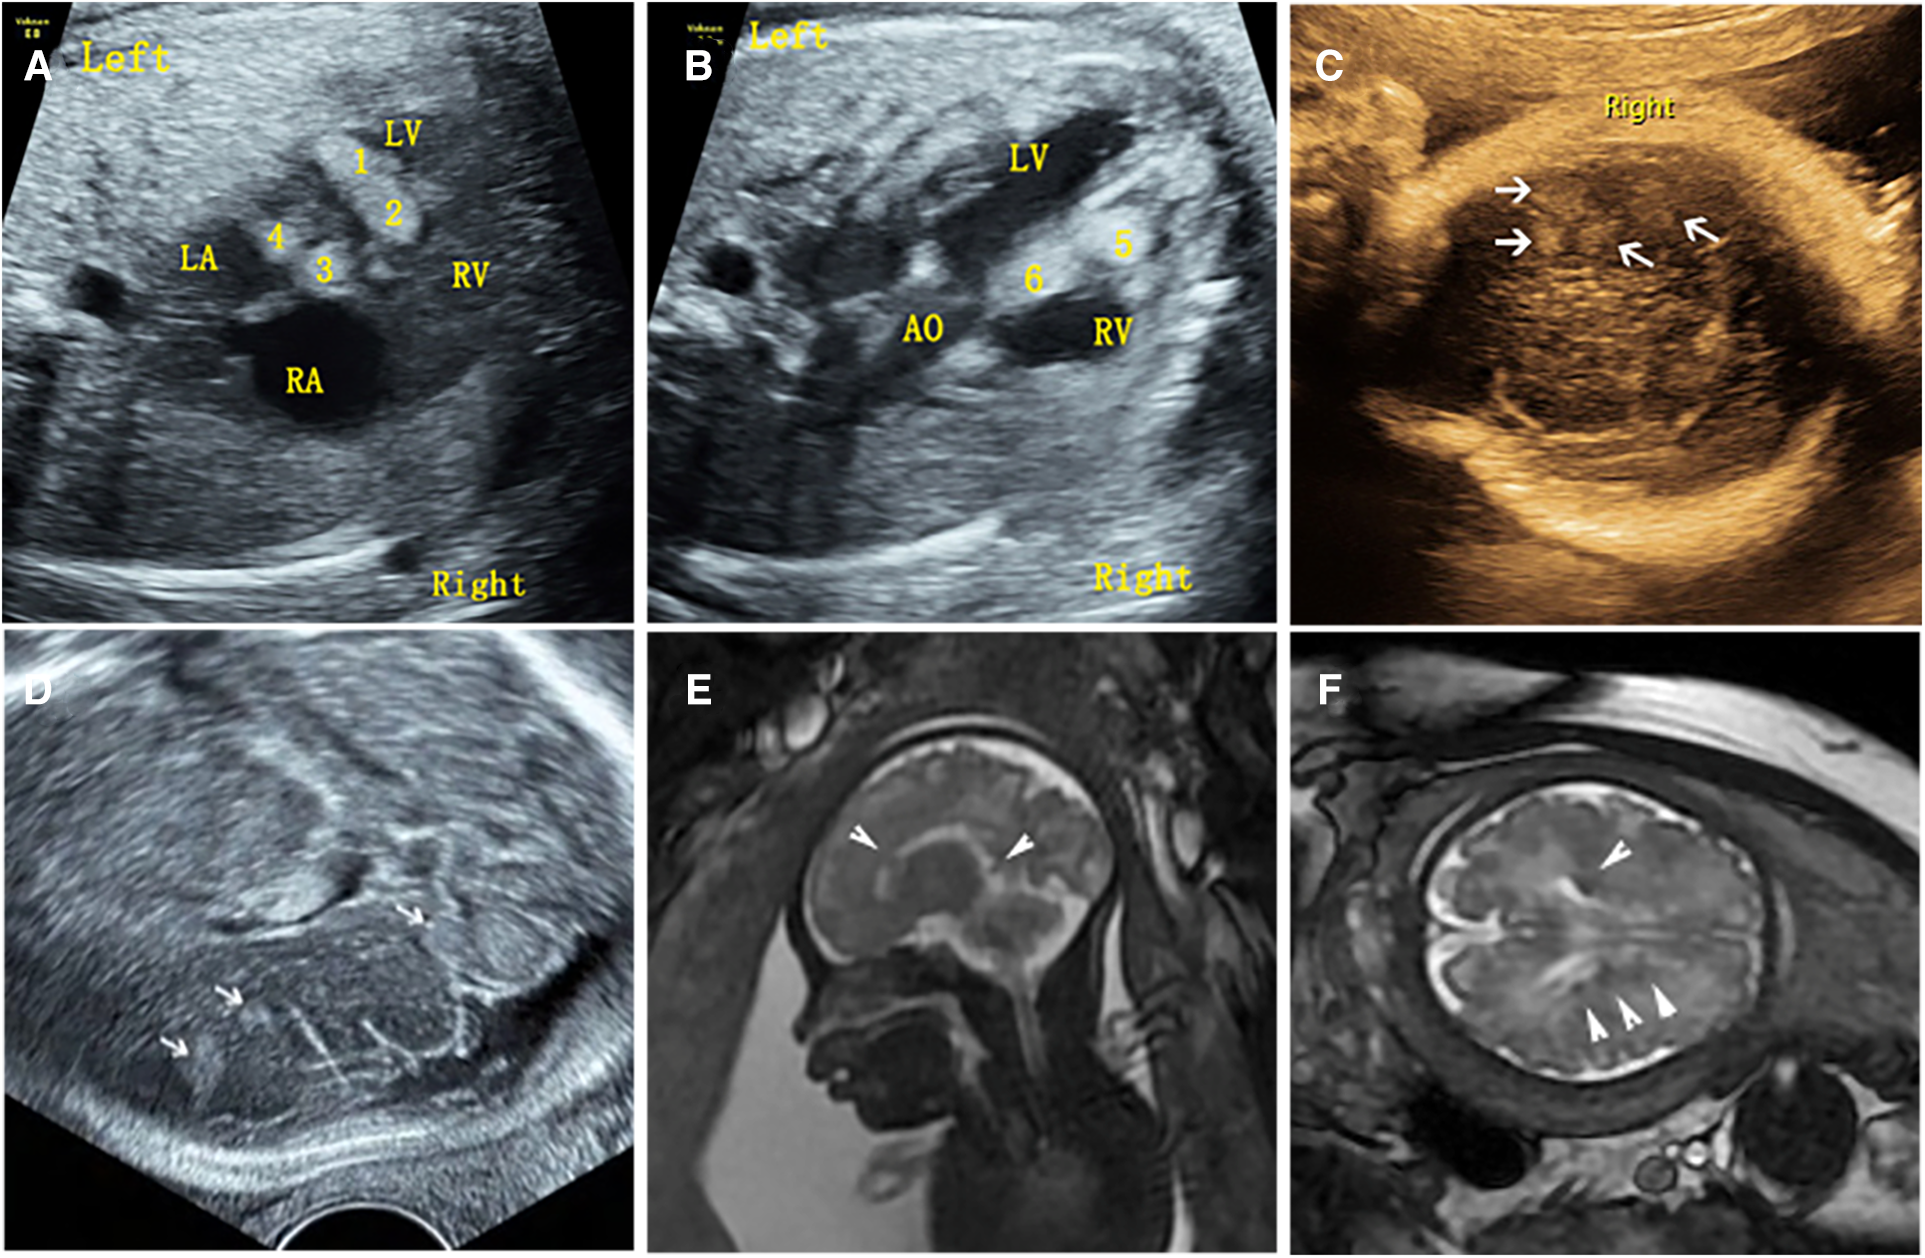

Figure 2

Ultrasound and MRI findings of multiple cardiac rhabdomyomas complicated with multiple cranial sclerotic nodules in the fetus (case NO. 51) at 31 weeks of gestation. (A) Multiple slightly hyperechoic nodules in the left ventricle of the fetal heart. (B) Multiple slightly hyperechoic nodules in the right ventricle of the fetal heart. (C) Multiple hyperechoic intracranial nodules of the fetus detected by transvaginal sonography. (D) Multiple hyperechoic intracranial nodules of the fetus detected by transabdominal sonography. (E) MRI sagittal T2-weighted image with multiple subependymal nodules. (F) MRI axial T2-weighted image with multiple subependymal nodules.

Of the 54 fetuses with CR diagnosed by ultrasound, 30 underwent fetal MRI. On ultrasound, 11 cases displayed intracranial nodules, often appearing as hyperechoic or slightly hyperechoic nodules, typically occurring in multiples (Figure 2). The majority (90.9%) were in the brain parenchyma, and some (27.3%) in the subependymal area. Prenatal brain MRI confirmed 15 cases of intracranial sclerosing nodules, which displayed a high signal on T1 and a low signal on T2 (Figure 2). A substantial portion (40%) was located in the brain parenchyma, while the majority (93.3%) were in the subependymal area. One case showed multiple intracranial lesions on ultrasound but no MRI abnormalities (Figure 4); postnatal MRI later confirmed intracranial nodules. Ultrasound combined with MRI identified 16 fetuses with intracranial sclerosing nodules, with 14 having TSC1/2 gene mutations, and 2 diagnosed with Tuberous Sclerosis Complex (TSC) postnatally. Among 14 fetuses without prenatal intracranial nodules, 7 had TSC1/2 gene mutations, 6 tested negative for the TSC gene, and 1 did not undergo TSC genetic testing, being diagnosed with simple CR after a 5-year follow-up. Moderate agreement was seen between ultrasound and MRI in diagnosing TSC (K = 0.60). Sensitivity for ultrasound, MRI, and the combination of both in predicting CR with TSC was 47.83, 65.22, and 69.57, respectively (Table 1, Figure 5). The corresponding AUC values were 0.739, 0.826, and 0.848, with MRI demonstrating higher sensitivity in detecting intracranial sclerosing nodules in fetuses with CR. No significant difference in AUC values was observed among the three groups (P > 0.05).

It is worth mentioning that our study found difference between ultrasound and MRI in detecting fetal intracranial lesions. Previous studies have suggested that subependymal nodules are more easily identified on fetal imaging, however, subcortical lesions are more commonly detected in postnatal brain MRI (10). Our analysis of imaging data found that prenatal ultrasound mostly identifies nodules in the brain parenchyma (90.9%), while prenatal brain MRI primarily detects subependymal nodules (93.3%). For example, ultrasound detected brain parenchyma nodules in case NO. 51, while brain MRI found subependymal nodules (Figure 2). In case NO. 13, prenatal ultrasound identified multiple intracranial nodules, whereas prenatal brain MRI didn't show any abnormalities. However, postpartum ultrasound and neonatal brain MRI revealed intracranial nodules (Figure 4). These phenomena suggested that ultrasound might detect specific fetal brain lesions not visible on MRI, warranting further investigation.